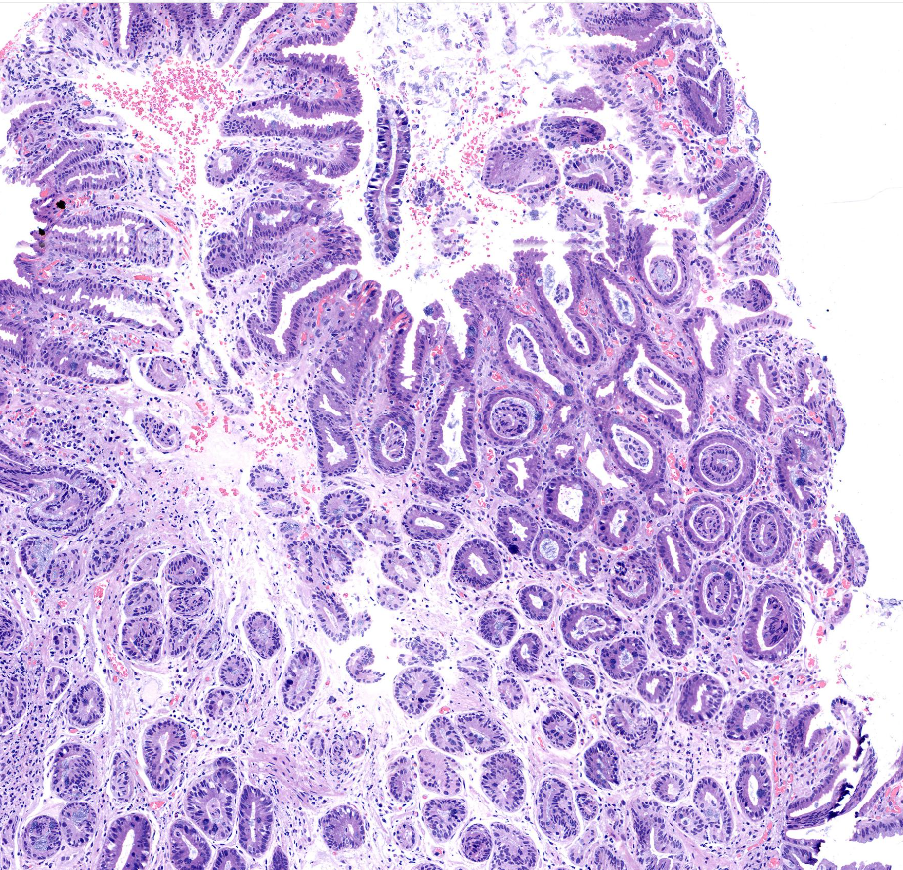

胃窦体交界表浅平坦病变

胃窦体交界活检

窦体交界表浅平坦病变1*1.2cm.

标记排除高级别

倾向炎症反应性增生

慢性炎症,伴有肠化。

高瘤

深切之后局灶高瘤

高级别

高瘤变。